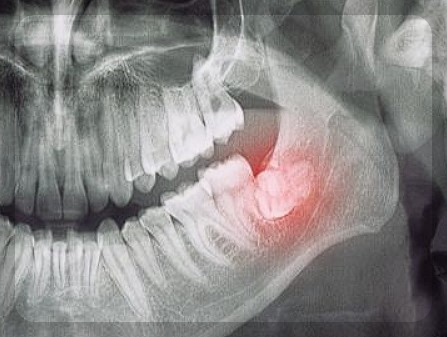

효과적인 구강암의 치료방법은 조기발견 입니다. 구강암에서 가장 많은 비중을 차지하고 있는 설암은 암이 발생한 부위의

혀를 일부 제거하여야 합니다. 암 이 클수록 제거해야 하는 범위가 커지기 때문에 초기에 발현할 수록 암이 적게 퍼져 치료가 수월하게 이루어 집니다.

조기에 발견하면 기능장애를 최소한으로 하면서 완치될 가능성이 높아집니다. 암세포 조직을 제거하기 위한 목적으로 구강 본연의 기능을 최대한 보존하는데 치료 목적을 가지고 있습니다. 초기에는 수술을 받아도 기능장애가 거의 없고, 방사선 치료보다는 수술을 하는 것이 최우선 입니다.

구강암을 수술하게 되면 얼굴 형태나 기능에 문제가 생길 수 있고, 피부/혈관/ 뼈 이식하는 치료가 동시에 이루어집니다. 재건수술과 암 치료가 동시에 이뤄지기 때문에 난이도가 높은 축에 속합니다. 모든 암이 조기 발견이 중요하듯 구강암도 치과 검진을 정기적으로 받고 , 입안에 궤양이나 염증이 장기적으로 진행될 때에는 병원을 방문하도록 합니다.